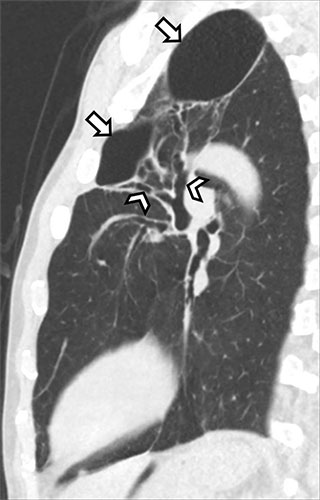

Sagittal noncontrast CT image in a 60-year-old man with a history of daily marijuana use but no reported cigarette smoking who presented with dyspnea and dry cough shows left upper-lobe bullae (arrows), with cylindric bronchiectasis (arrowheads) within a background of moderate centrilobular emphysema.

Marijuana and cigarette smokers share many imaging features, including findings of airway inflammation and emphysema. In marijuana smokers however, Dr. Koo said that a paraseptal-predominant pattern of emphysema is more often seen, as well as apical bullae that can enlarge with time, predisposing to rupture and pneumothorax.

“Most importantly, these features manifest in marijuana smokers at a younger age compared to cigarette smokers, possibly due to the higher concentration of particulates in marijuana smoke,” he added.